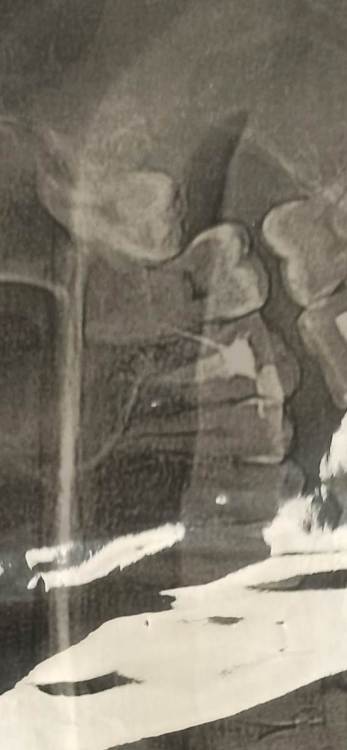

Здравствуйте, подскажите пожалуйста, стоит ли удалять верхние зубы мудрости. Был в двух разных клиниках, в одной сказали, что надо удалять, в другой, что не стоит. Никакого дискомфорта они не вызывают, болей нет. 28 лет. СпасибоScreenshot_2024-03-06-11-13-03-289_com_miui.gallery.thumb.jpg.4c57e196865248069b5846c81165aa65.jpg

В Вашем случае, когда нет нижних восьмерок, верхние абсолютно бесполезны, даже если вылезут и встанут на свое место. Но, находясь в такой позиции велика вероятность, что со временем они будут портить дистальный отдел седьмого зуба, а уж семерки явно жалко. Поэтому смысл убрать восьмерки в профилактических целях есть. Но профилактика тоже штука не стопроцентная. У кого-то такой зуб всю жизнь сидит в этом месте и нет никаких проблем, а у кого-то удаляют и семерка все равно с кариесом оказывается. Поэтому решайте сами.